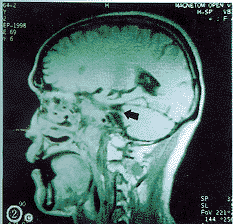

(1)小脑脑桥角肿物:指在岩锥或岩枕缝的后方或上方,见弧形隆起的软组织肿物。该肿物在平扫的CT上呈中等密度,与其周围脑结构的密度对比差,故易漏诊;在增强的CT上呈高密度;在平扫的MRI上呈中、高信号,增强后信号更高,显示更清晰,见图1,2。

a轴位 b冠状位 c矢状位

图1 增强的T1加权MRI示复发性鼻咽癌累及右侧小脑脑桥角(黑、白箭头)

肿物在小脑脑桥角的近内侧者28例(图1),在近内耳门者2例。肿物最大直径为1.0~6.5?cm。在原始的影像学报告书上诊断小脑脑桥角占位的仅6例。2例小脑脑桥角肿物在增强和不增强的MRI上均显示其是由海绵窦沿三叉神经向后蔓延达桥池的(图2a),其中1例尚显示其海绵窦的肿物是同侧的NPC咽旁复发经由扩大的卵园孔沿下颌神经向上蔓延而来的(图2b),此种沿神经扩展的现象在CT上即使增强也不能显示。6例于放射治疗后复查MRI或增强CT,其中5例CPAI消退(图2c),1例缩小。

(2)占位效应:指CPAI较大,挤压毗邻的脑干,使之向健侧移位(图1a),环池两侧不等宽。本组10例阳性(33.3%)。